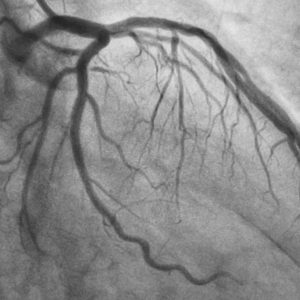

Ptca is an acronym that stands for Percutaneous Transluminal Coronary Angioplasty, a minimally invasive treatment used to open up blocked coronary arteries in the heart. In simpler terms, it's a procedure that helps restore blood flow to the heart muscle by inflating a balloon to widen narrow or blocked arteries. This life-saving treatment has become increasingly popular within the medical community due to its effectiveness and relatively low risk.

The success of Ptca lies in its simplicity and the access it provides to the blocked arteries. A stent is a small, mesh-like tube that is gently inserted into the artery through a small incision in the leg. It is then guided to the blocked section of the artery before being inflated at various points to ensure its proper positioning. Once the arteries are widened and blood flow is restored, the stent remains in place to prevent further blockages.